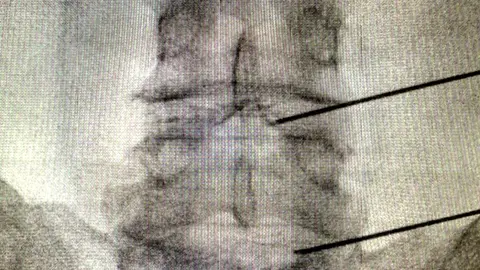

Los dos nuevos procedimientos incluidos en la cartera de servicios de la Unidad del Dolor son mínimamente invasivos y solo requieren de anestesia local